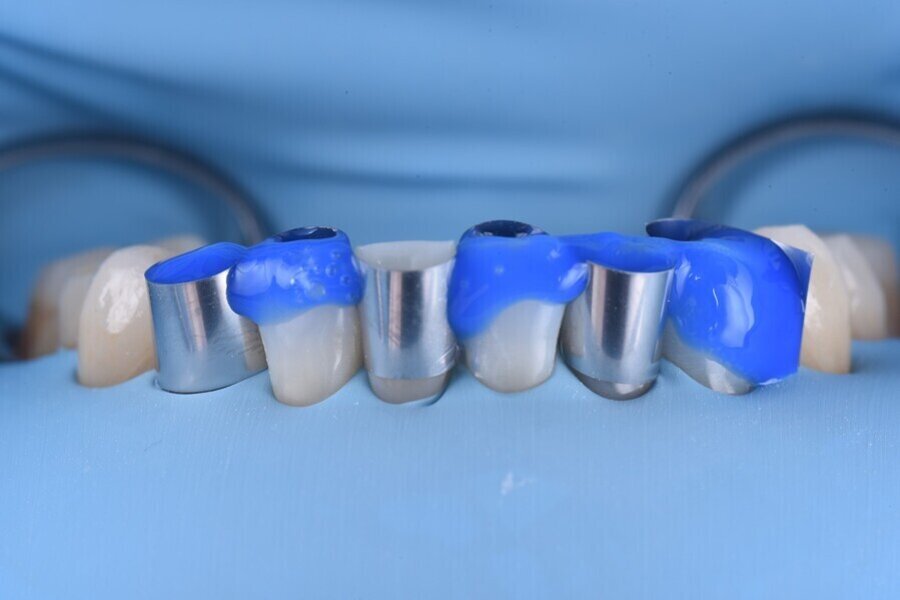

V rámci digitálního designu navržené rekonstrukce byla provedena částečná redukce dolní poloviny bukální plochy plánovaných korunkových náhrad, aby bylo umožněno vrstvení keramiky pro dosažení co nejlepšího estetického výsledku (obr. 12 a 13).

Obr. 12: Kontrola tloušťky.

Obr. 13: Konečná rekonstrukce (s prostorem pro frontální stratifikaci).